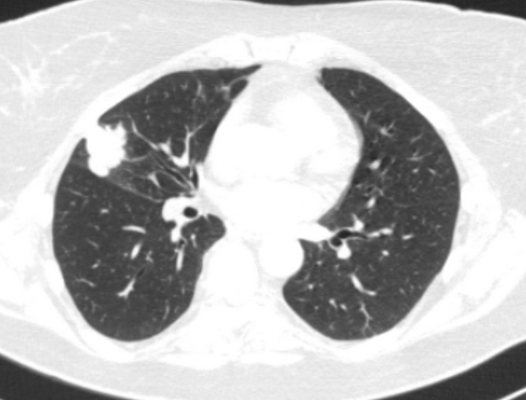

Лимфомы медиастинальной локализации не всегда диагностируются при рентгенологическом обследовании. Компьютерная томография, более детально, чем обзорная рентгенография позволяет рассмотреть конгломерат опухоли, увеличение лимфоузлов средостения, вовлечение паратрахеальных, трахеобронхиальных, прикорневых лимфатических узлов. Диагностическая значимость магнитно-резонансной томографии в верификации лимфом средостения признается не всеми авторами.

КТ ОГК. Объемное образование в средостении (патологически измененный лимфоузел), подтвержденная лимфома.